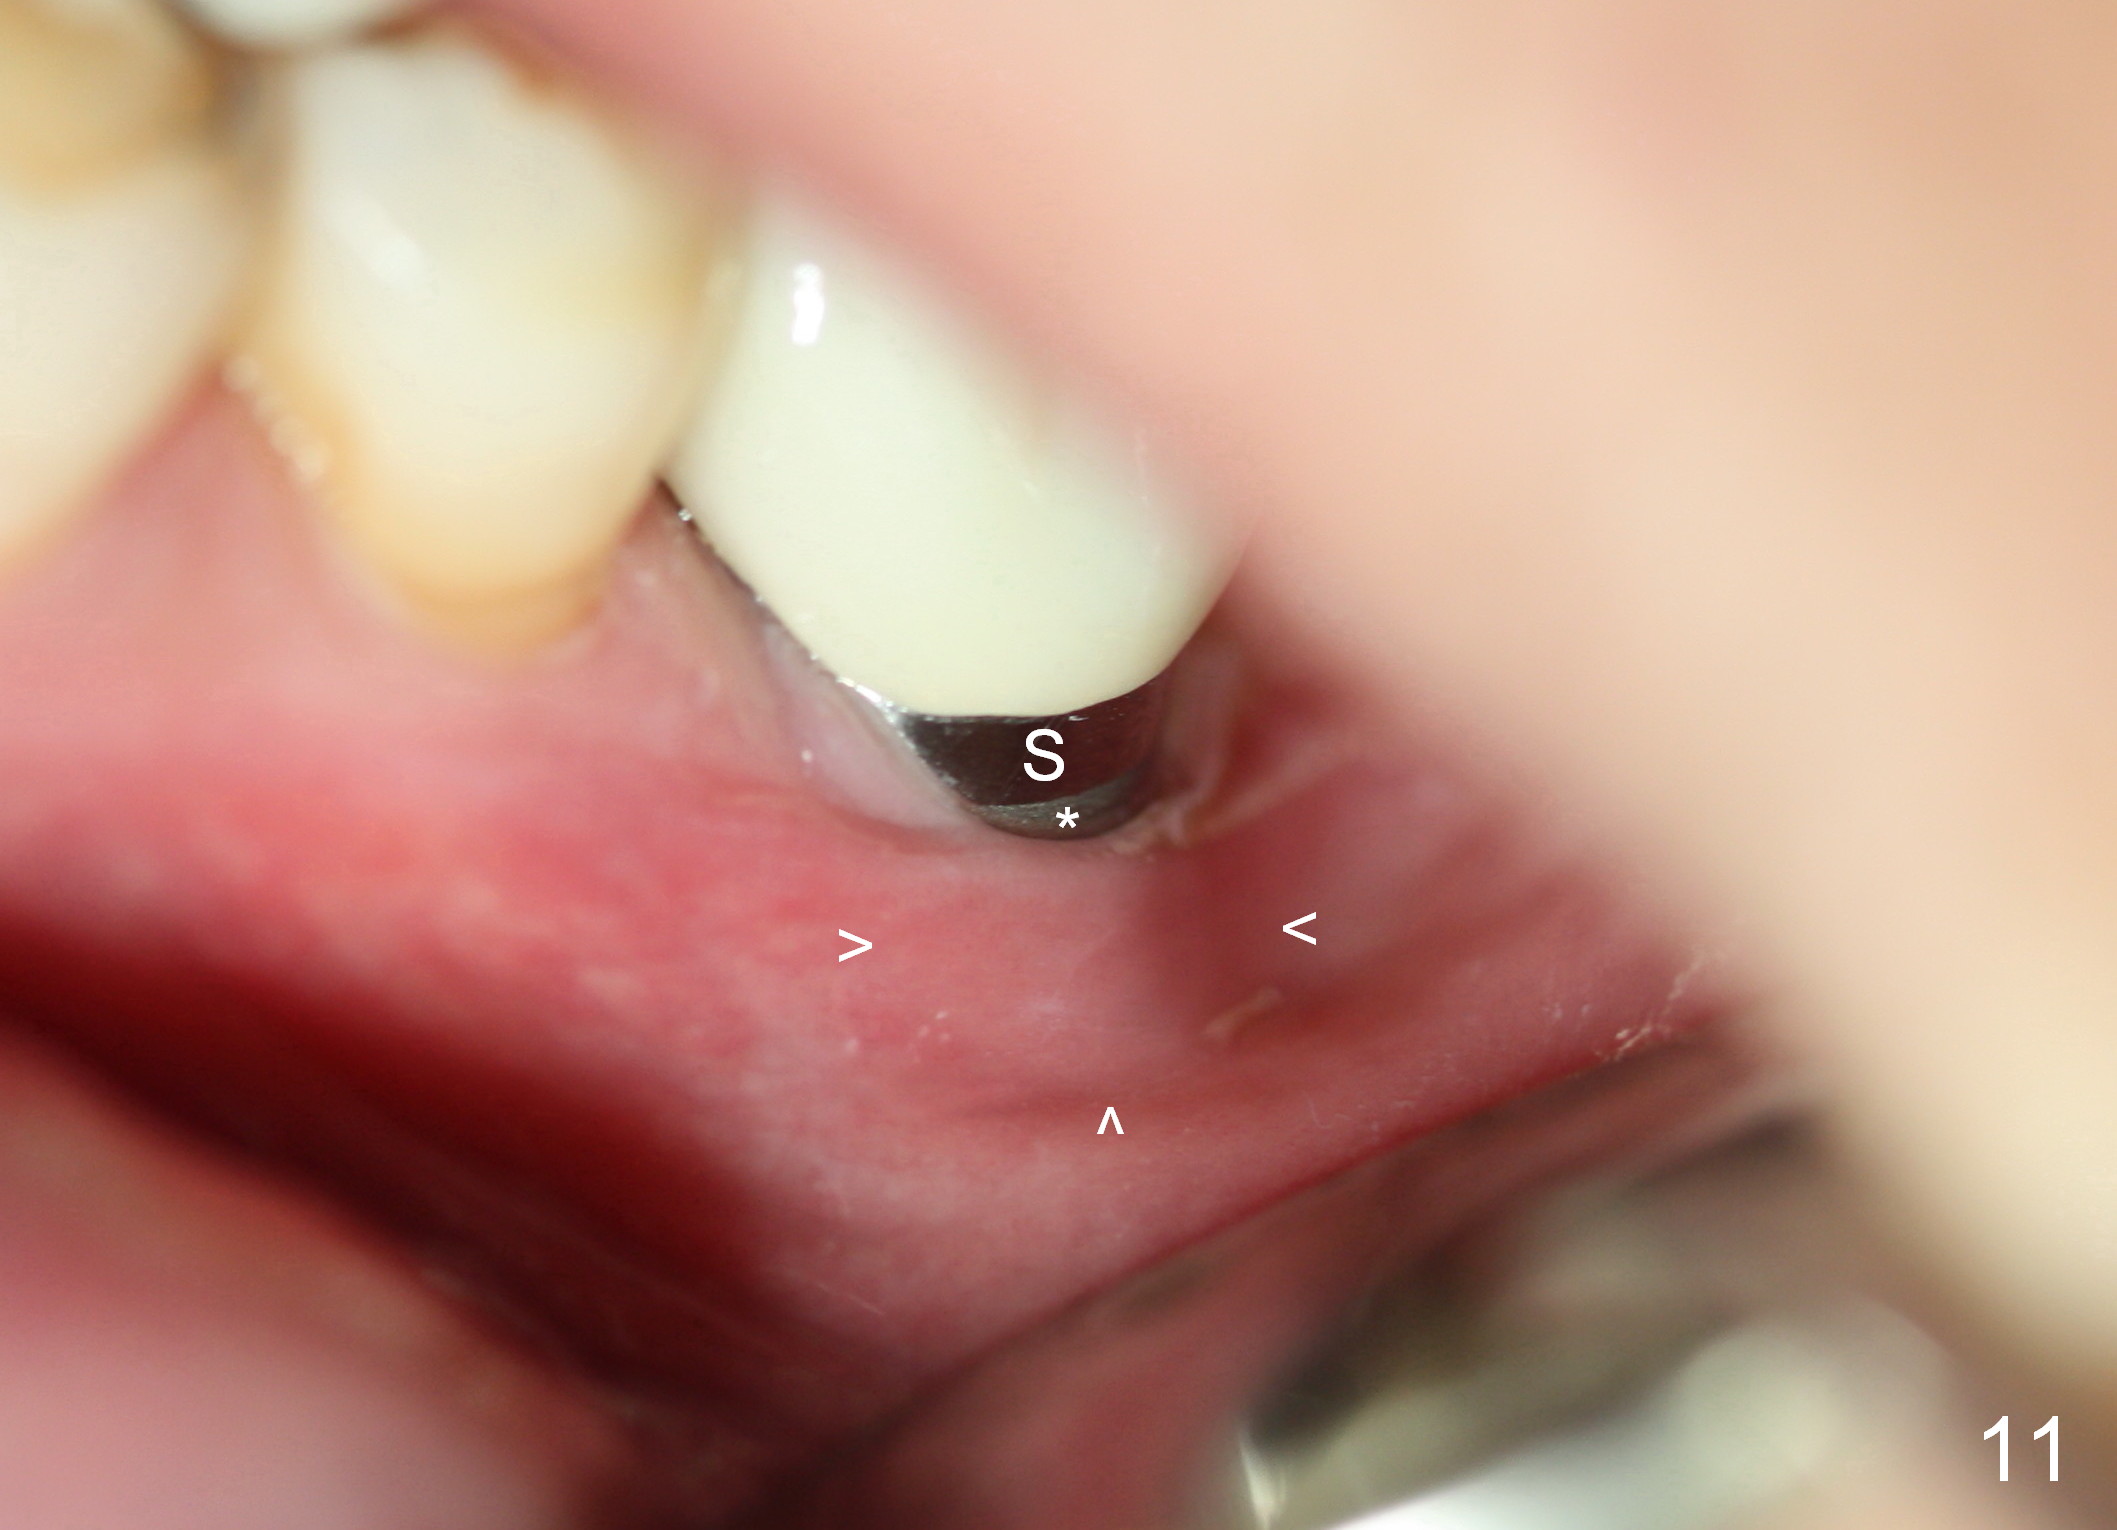

The patient returns for #19 restoration one year postop. The distal coronal threads appear not covered by bone (Fig.10 *) with distobuccal gingival recession (Fig.11). The buccal bulging (Fig.11 arrowheads) may be related to thin or no buccal plate. Bone graft at time of immediate implant may decrease the likelihood. In addition, the implant is placed buccally slightly (Fig.12). The gingival recession appears to have decreased 1 year 9 months post cementation (Fig.13). A thick keratinized gingiva forms around the implant at #8 1 year 11 months post cementation. There seems to be no bone loss 2.5 years post cementation (Fig.14,15, as compared to Fig.10)